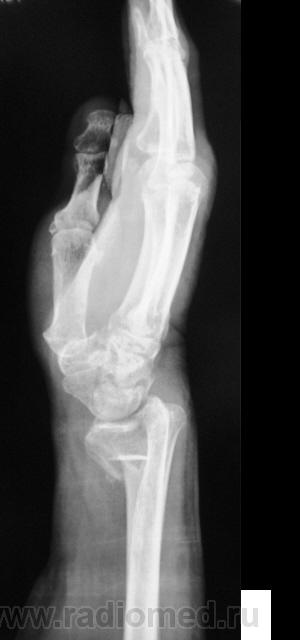

Пусть интересуется... Гипс снят рановато, стояние отломков - неудовлетворительно,хотя бывает и хуже

Если срок сращения 4 недели, то признаки консолидации выражены соответственно сроку достаточно хорошо. Перелом компрессионный, поэтому произошел вывих в л/л суставе. Можно или нет его было устранить в амбулаторных условиях - судить не берусь. Осколок кортикала в луче "захряснет", может, рассосется - ничего страшного.

неприятная ситуация(особенно если не было первичной репозиции) есть оппределенные правила ведения таких переломов, первичный снимок, сразу после репозиции, через 4-5 дней после репозиции и если нет вторичного смещения в гипсе то через 4-5 недель уже без гипса. ситуация на данный момент спорная, лучше наложить аппарат Илизарова для дальнейшей иммобилизации и профилактики контрактуры л\зап сустава. если возраст пациентки почтенный, то гипсовая иммобилизация доолжна быть продлена до 8 недель.